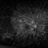

- Fluorescein angiography imaging of a 27-year-old male with acute inflammation as part of Vogt-Koyanagi-Harada Syndrome.